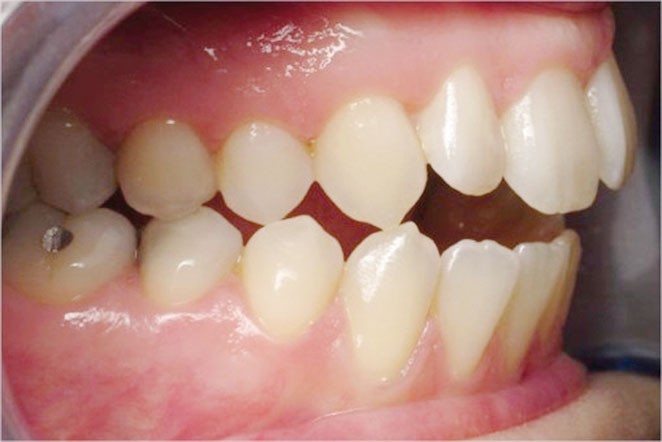

6 mois plus tard

L’esthétique faciale de la patiente s’est nettement améliorée (fig. 7, 8, 9 et 10). On remarquera la réduction du sourire gingival…